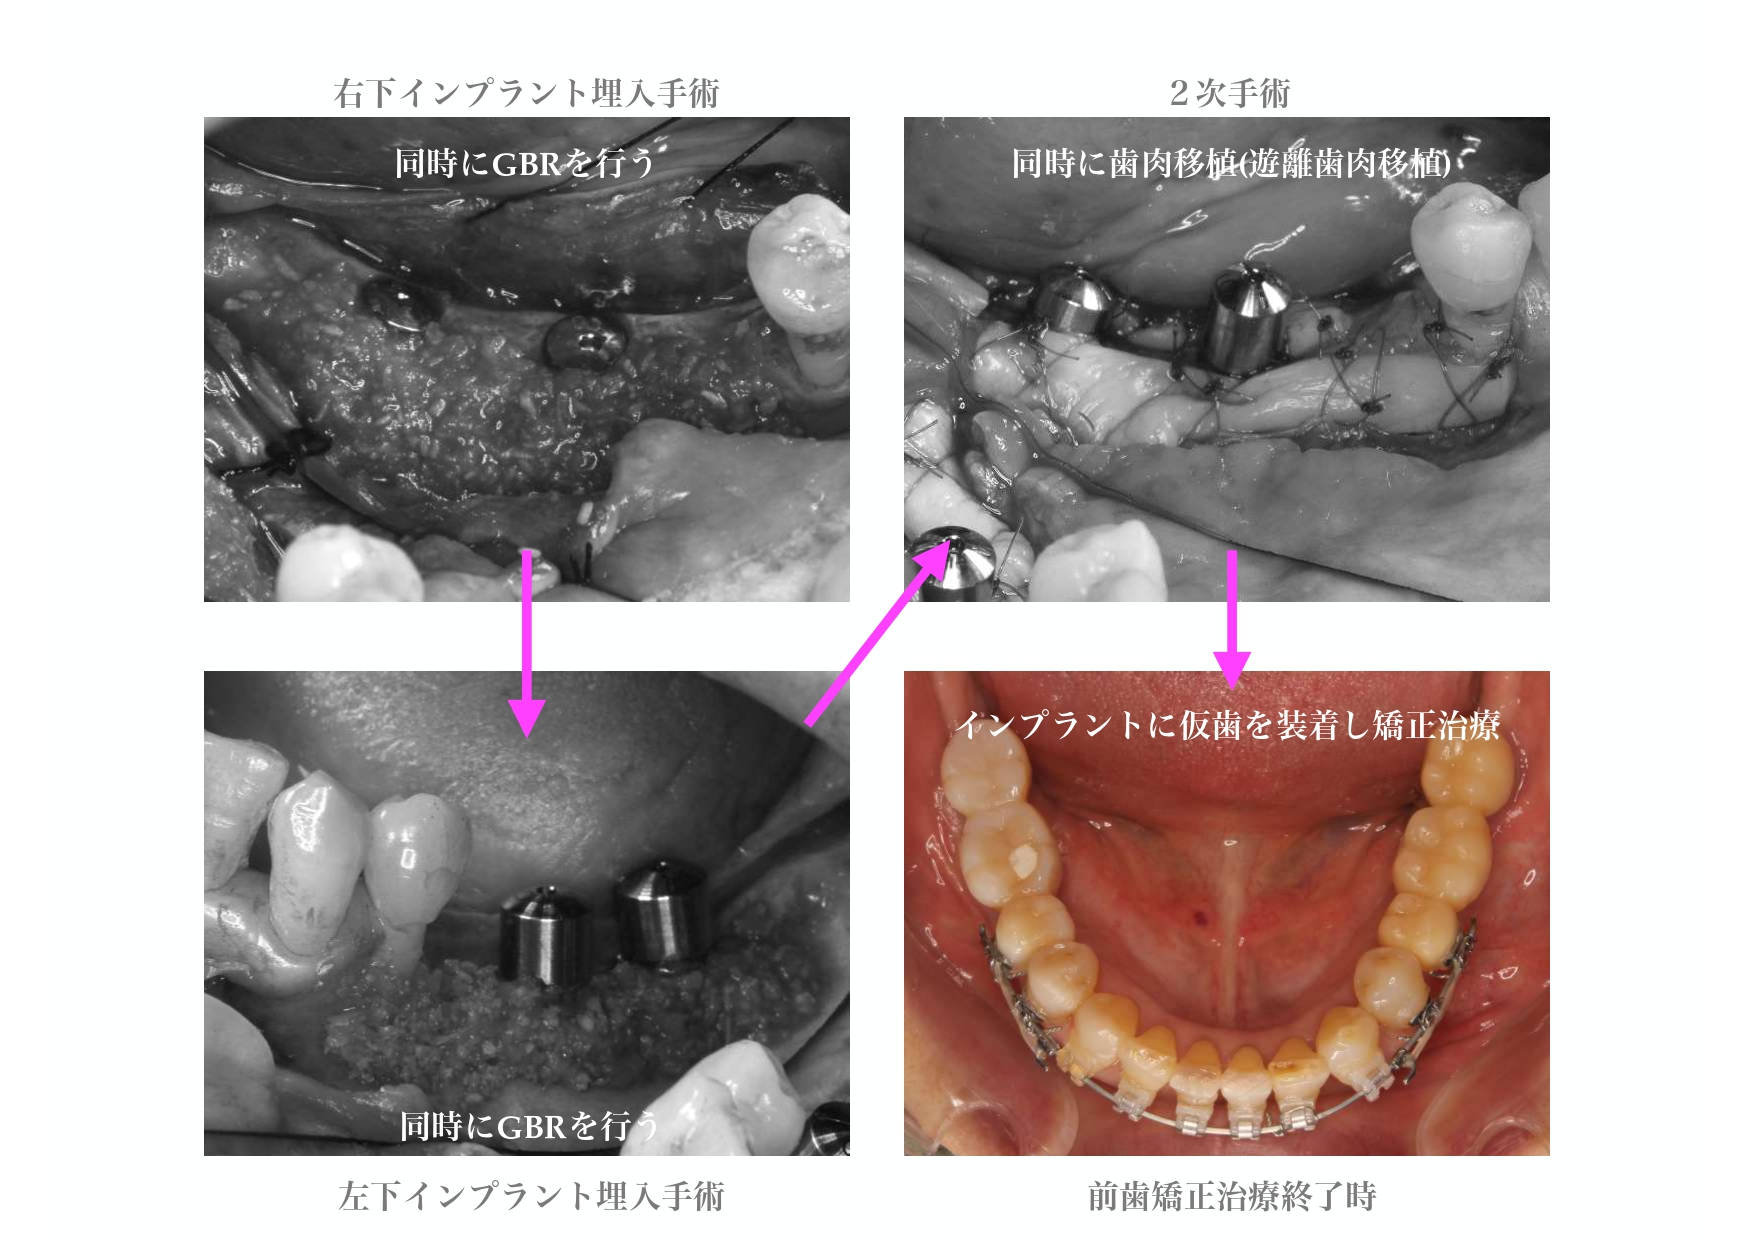

| 治療内容 | 精密検査、コンサルテーション、歯周初期治療、治療用義歯、インプラント4本、GBR、2次手術時歯肉移植、仮歯、部分矯正、上部構造6本、自費コンポジットレジン修復、保定 |

治療詳細